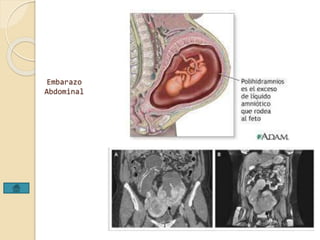

Embarazo

Ampular

Ovárico

Tubarico

Embarazo Cervical

Abdominal